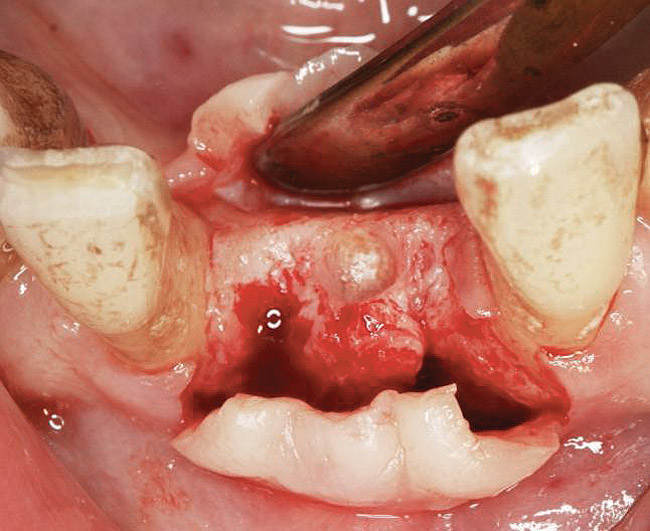

A round bur is usually used to mark the position where a 2-mm twist drill will be applied (Figure 1). Then the twist drill is employed to penetrate the cortical and trabecular bone (Figure 2). This provides information with respect to cortical bone thickness and medullary trabecular bone density. The amount of bone debris found on the twist drill can be interpreted as an indicator of bone quality (eg, the less debris and a more bloody appearance means softer bone). Four types of mineralized bone have been described by Misch (Table 1):1,2

When a 2-mm twist drill is used to full depth of the osteotomy (eg, 10 mm), it is difficult to change osteotomy angulation with a twist drill. If a correction is necessary, a side-cutting bur (eg, Lindemann) should be used (Figure 9). Furthermore, if there are doubts as to closeness of the osteotomy to adjacent teeth or vital structures, then a radiograph with a guide pin in place should be obtained.30 Ultimately, the angulation and location of the osteotomy should be consistent with design of the future restoration.31